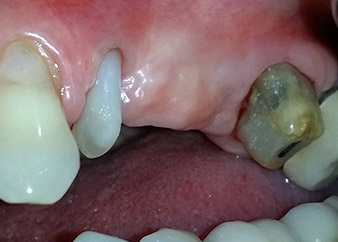

58-годишна пациентка се оплаква от болка и повишена подвижност в нейния мост върху зъб 24 с функция на абатмънт. На лице е периодонтално възпаление с дълбочина на джоба 7 mm мезиобукално и повече от 12 mm дистално, както и включена 3 градусова фуркация. Освен това, рентгенографията показва обширна периодонтална лезия около апикалната зона на (друго място) предварително ендодонтски обработен зъб 24 (Фиг. 1).

Една година по-късно, зъби 25 и 26 са екстрахирани в следствие на травма и поради ендо-перио причини, преди поставянето на моста. Комбинирана ендо-перио лезия е диагностицирана за зъб 24 от неясна етиология. Пациентката иска да задържи нейния мост с абатмънт на зъби 24 и 27 и не приема окончателна, подвижна протеза. По този начин, взаимно решихме да положим всички усилия да запазим и двата зъба, въпреки лошата прогноза за тях, която е базирана на рентгенографски и клинични резултати.

След един месец, в деня на операцията, болката и възпалението в зъб 24 е минимално, но подвижността в Miller class 2 е на лице. След отваряне на ламбата и почистването на периапикалната и перирадикуларната тъкани, обхватът на костния дефект стана очевиден (Фиг. 2 и 3).

В букалния корен, цялата вестибуларна и дистална кост липсва. Захващането е значително ограничено до палатиналния корен, подчертавайки предварително лошата прогноза. Зъб 27 също откри намалено хоризонтално захващане и минимално апикално разреждане (Фиг. 1) без клинични симптоми.